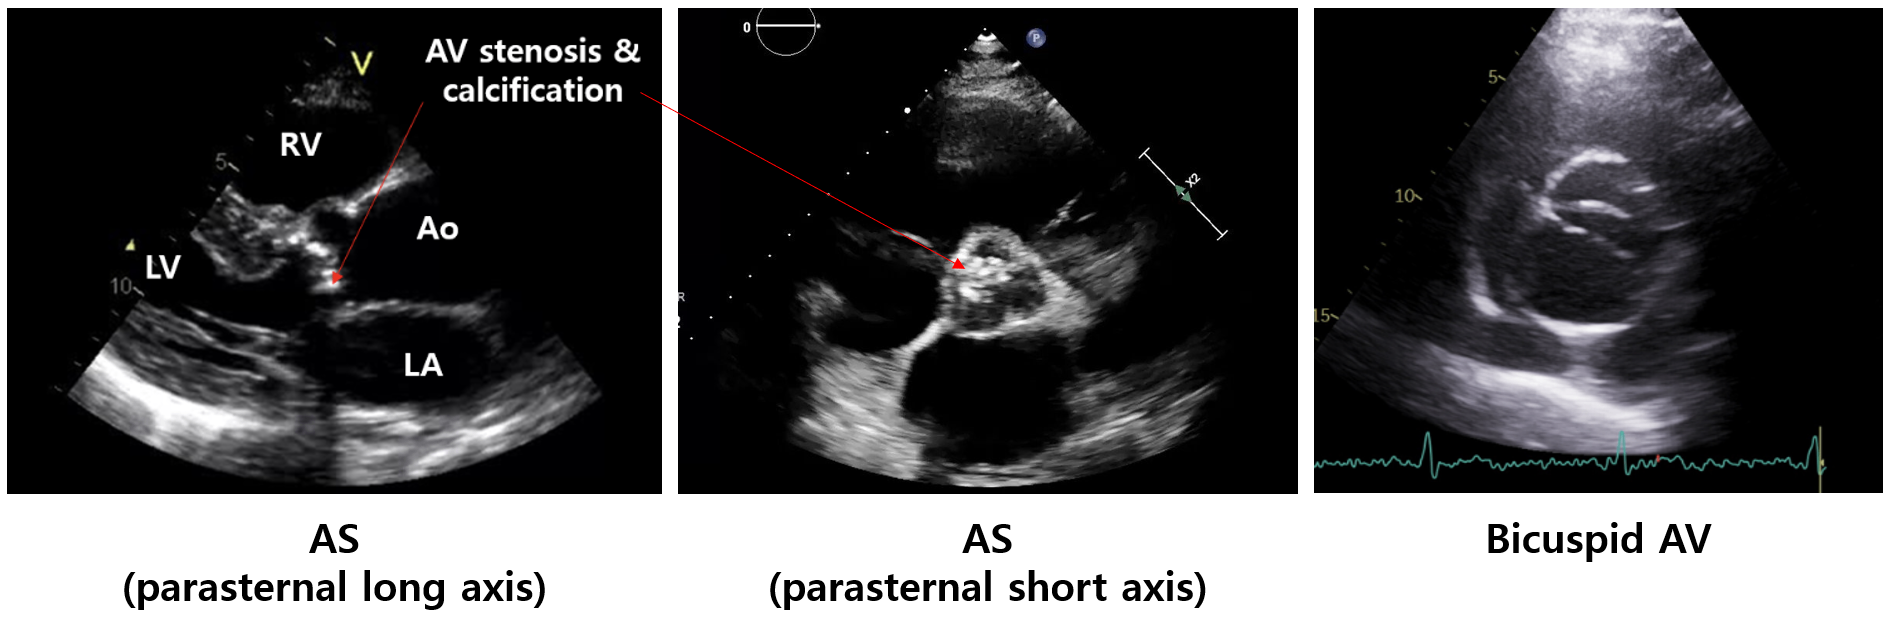

1) 경흉부심초음파(transthoracic echocardiography, TTE): 1st line

(1) AV 형태(AV area, calcification, bicuspid valve 유무 등) 확인 가능

(2) LV hypertrophy

(3) 기타: AV 혈류 속도, LV-aorta 압력차이, LV/RV 기능, 폐동맥압 등